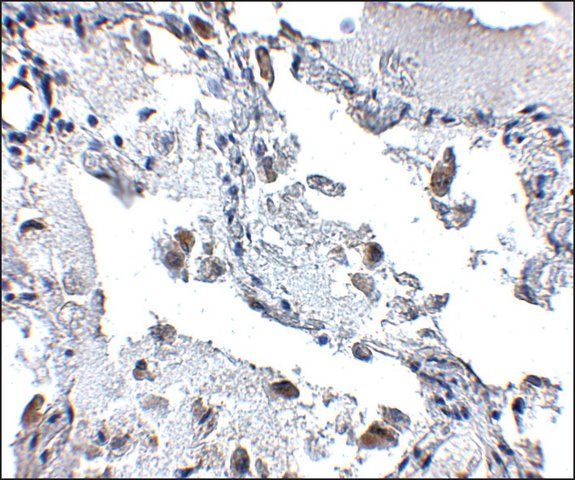

SH3-domain GRB2-like (endophilin) interacting protein 1 (SGIP1) is expressed in the brain. It is rich in proline and highly conserved between species. The gene encoding SGIP1 is localized on human chromosome 1p31.3.

SH3-domain GRB2-like (endophilin) interacting protein 1 (SGIP1) has been shown to be a contributing factor for obesity-related elements in humans. It interacts with intersectin 1 (ITSN1) which is an adaptor protein and takes part in clathrin-mediated endocytosis.

| technique(s) | immunohistochemistry: 1:20- 1:50 |